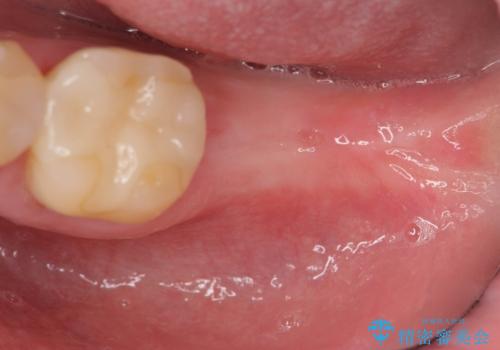

歯の抜去を行い、骨の造成を含めたインプラントによる咬合機能の回復を図ります。